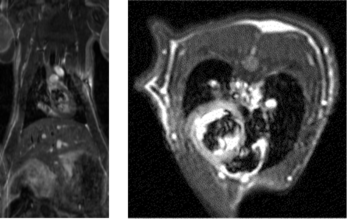

青>黄>赤>白 の順に透過性が大きくなっています。 - 脳梗塞ラットのfMRI

左:T2強調画像 白い部位は脳梗塞、オレンジ色の部位は有意(P<0.01)に信号強度が上昇した部位を表しています。

右:脳梗塞モデル(手術一週間後)の左右大脳皮質感覚野における信号強度の平均と経時変化 梗塞病巣の観察される右側では電気刺激に応じた反応が得られていないことがわかります。 - コモンマーモセットの脳の画像